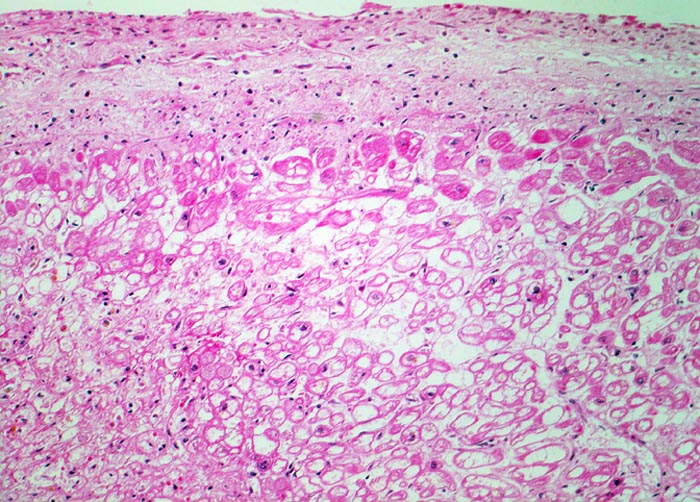

PathoPic – image database / PathoPic ID 4611 - ischämische Herzmuskelschädigung: tubuläre Degeneration

ischämische Herzmuskelschädigung: tubuläre Degeneration

Luminaler Anteil der linken Herzkammer: Das unmittelbar subendokardial lokalisierte Myokard wird aus dem Herzblut per diffusionem mit zusätzlichem Sauerstoff versorgt. Bei einem Verschluss der Koronargefässe ist dieses Myokardareal von der Nekrose ausgespart und zeigt lediglich Zeichen der ischämischen Schädigung. Ischämisch geschädigte Muskelfasern mit erhaltenen Kernen und blasigem vakuolisiertem Sarkoplasma (= tubuläre Degeneration = Holundermarkzellen = massive Glykogenspeicherung).

Diagnose eines Myokardinfarktes vor 4 Tagen.

Die hypoxisch bedingte vakuoläre (=tubuläre) Degeneration beruht auf einem Verlust der Myofibrillen und Glykogenspeicherung. Die zentral leeren Myokardzellen werden auch Holundermarkzellen genannt. Die veränderten Kardiomyozyten sind noch vital aber können sich nicht mehr kontrahieren. Das Auftreten der vakuolären Degeneration ist korreliert mit Herzinsuffizienz.